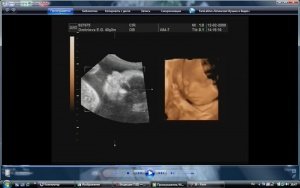

23 неделя беременности

На этом этапе Вы уже можете отметить ногтики у плода, они почти полностью сформировались. Кроме этого его пушковые волоски потемнели. Ваш кроха вырос практически до 30 см, а его вес уже целых полкило!